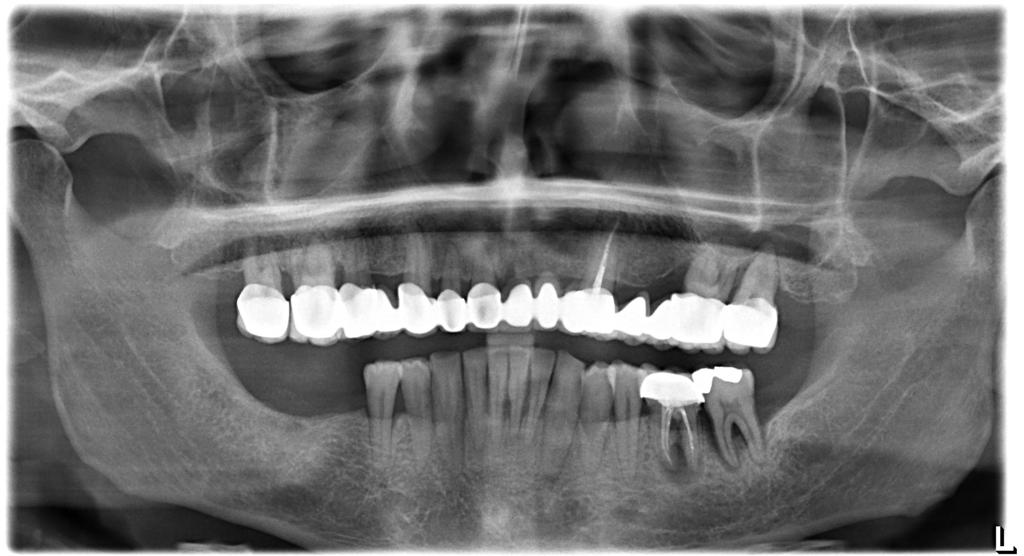

Case Presentation: A 42-year-old male patient with high diabetes and heavy smoking-alcohol use presented with multiple tooth loss. These systemic health factors posed potential risks for implant treatment. However, successful implant placement with Naxis implants was achieved in sites 46-47 to address the patient's dental needs. Approximately two years later, implants were also placed in sites 36-37 using Naxis implants.

Post-Treatment Evaluation: The patient continued smoking and alcohol consumption after implant surgery. However, evaluation of the long-term stability and success rates of the implants, based on X-ray images taken five years later, revealed that the Naxis implants were securely maintained. This demonstrates that successful implant treatment is possible despite the negative effects of systemic health factors, with regular follow-up and periodontal care.